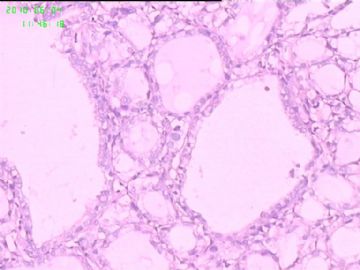

灰白结节2枚,其一2.5x1.8x1.5cm,包膜完整,内为褐色胶质,其二3x2.5x1.5cm包膜完整,切面灰白实性。附件镜下为后者。

可能楼主看到那些核的变化吧?但是没有其他支持的条件,还是应该是结甲。

就这几幅图似乎不够说明问题,细胞有一定的异型性,但是,最好能采到交界处的情况再判断。癌与非癌,最好能有组织结构与细胞异型性结合来看。

有些核透明,无其它特点,恶性证据是没有。